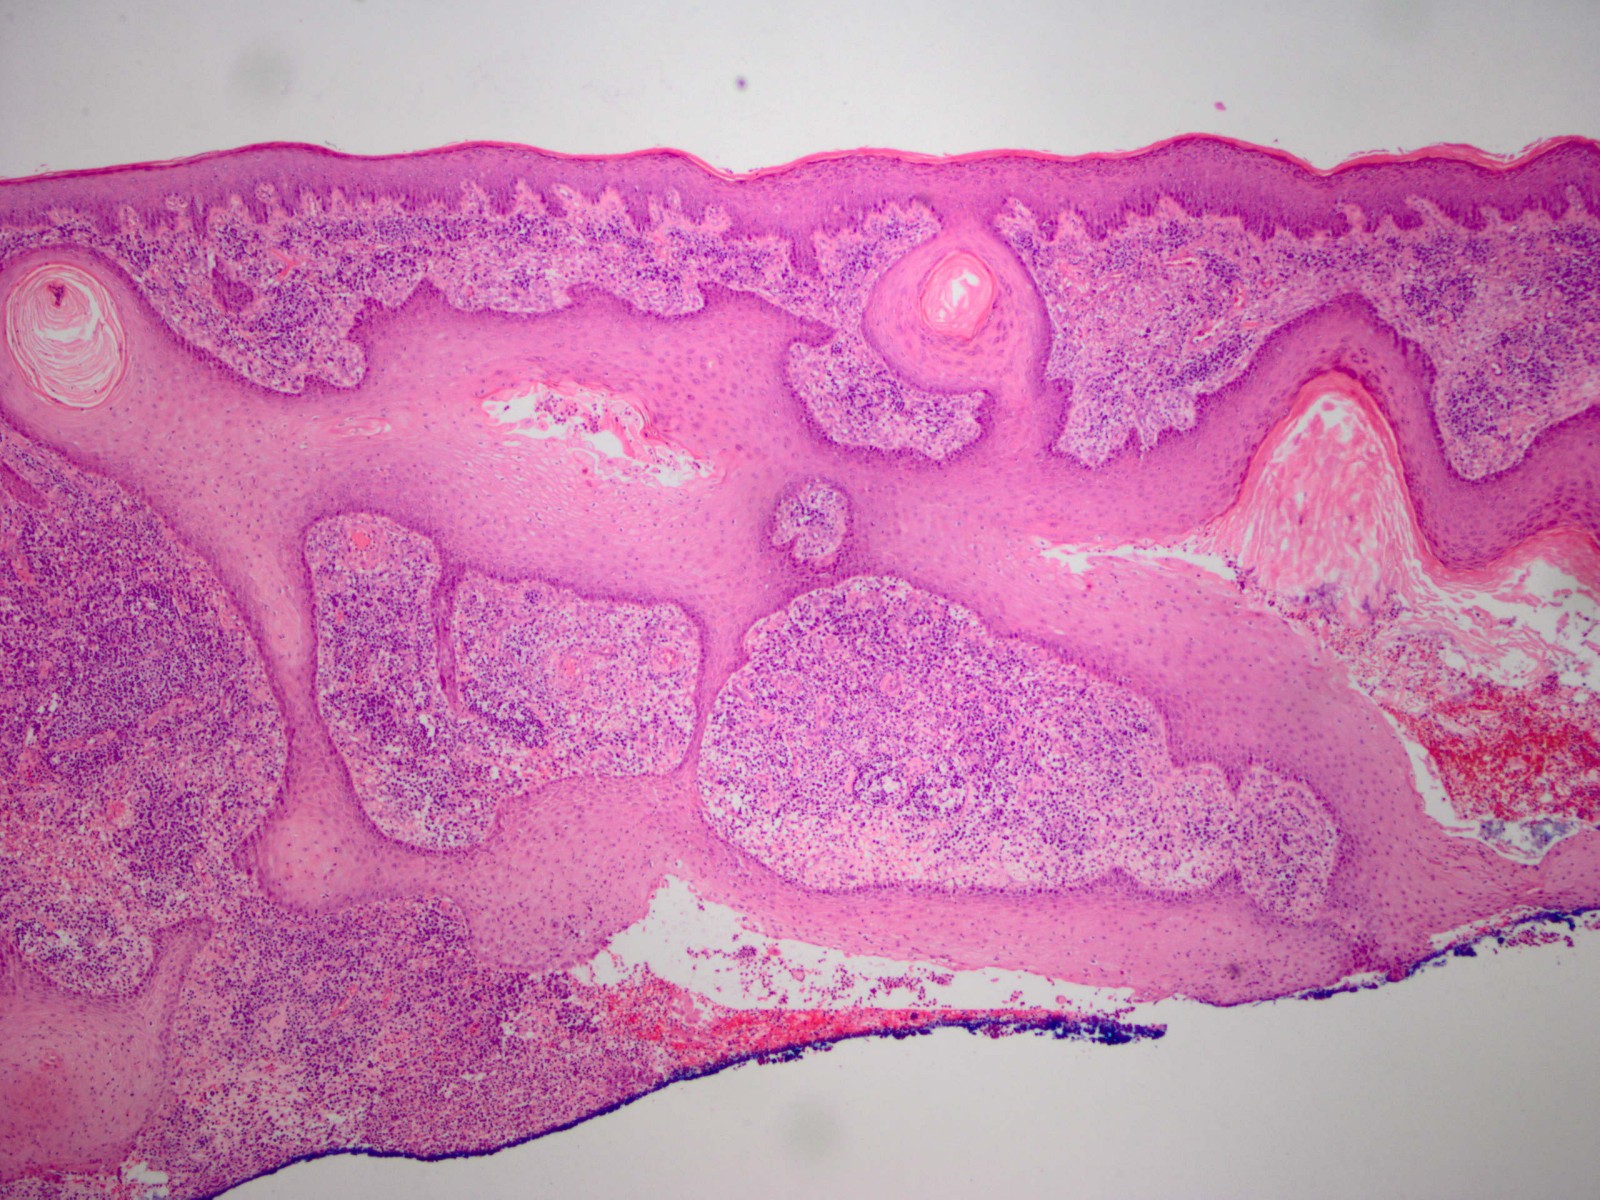

pyoderma gangrenosum. De histologie toont

supepidermale velden epitheel en oppervlakkige fistels omgeven door inflammatie.

Het ontstekingsinfiltraat vernietigt uiteindelijk de haarfollikels compleet

en ook grotendeels de epidermis en dermis tot ongeveer 3-8 mm diepte. Aan de

randen breiden deze plaques zich uit met een actieve ontstoken rand; centraal

treedt genezing op, het centrum wordt weer volledig geëpithelialiseerd maar

op een niveau onder de haarfollikels, met plaatselijk nog

cribiforme

resten van de originele epidermis. Omdat de haarfollikels volledig verwoest

worden, kan het niet nog een keer optreden in het zelfde gebied. De plaques

kunnen wel voortwoekeren over een groot oppervlak. De plaques laten littekens

achter die er uit zien alsof er een deroofing procedure heeft plaatsgevonden,

verzonken littekens bekleed met atrofische en haarloze epidermis.